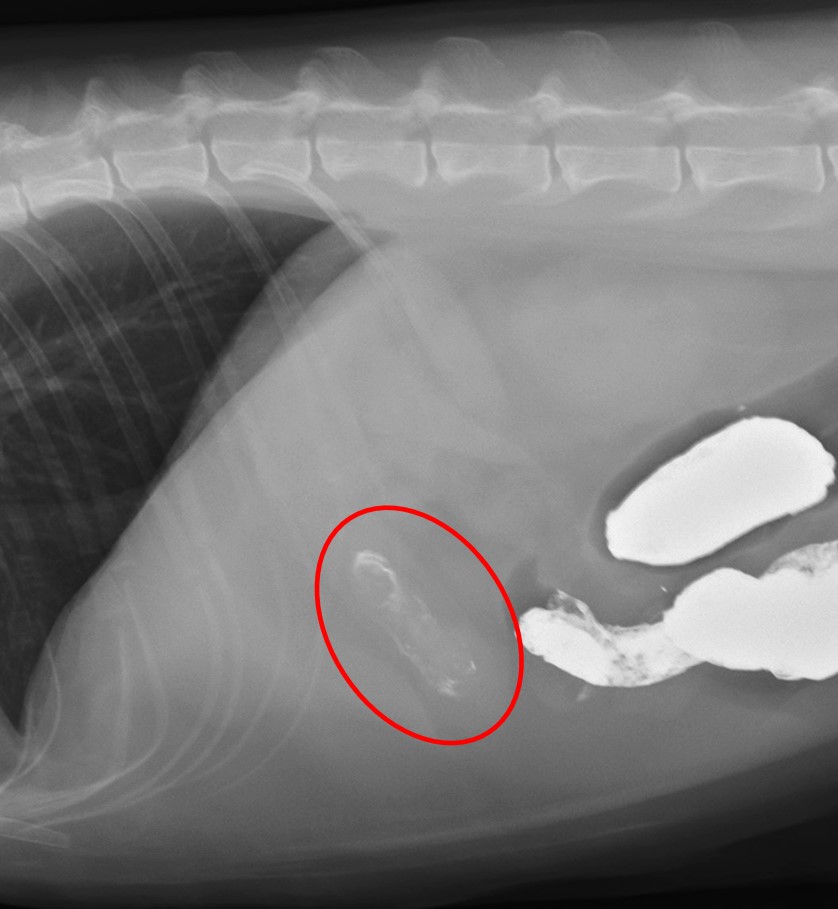

図6. 時間経過による画像の変化。胃から結腸まで造影剤が進んでいる(流出遅延あり)。

バリウムの胃からの完全排出は1〜4時間で行われます(バリウム造影剤のみの場合、固形食と混ぜた場合は7〜15時間かかる)。

そのため、胃内に4時間以上のバリウム造影剤のうっ滞がある場合、胃からの流出遅延を疑います(上記の図6)。

ただ、流出遅延は必ずしも病的要因だけではなく、精神的要因(不安・恐怖・騒音などによる交感神経刺激)によっても引き起こされるために注意が必要です。

これらを駆使して閉塞所見(上記の図4など)や流出遅延(上記の図6)、胃に滞留した異物(以下の図7)などを検出していきます。

図7. 造影された胃内異物(毛球に造影剤がまとわりついて造影増強効果が残る)。